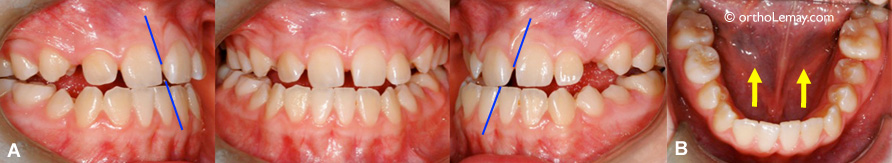

(A et B) Malocclusion et dentition avant le traitement; arcades étroites, chevauchement dentaire et manque d’espace sévères. (C et D) Après le traitement d’orthodontie et de chirurgie. Les arcades ont été élargies et toutes les dents sont logées dans les arcades dentaires (sans extractions).